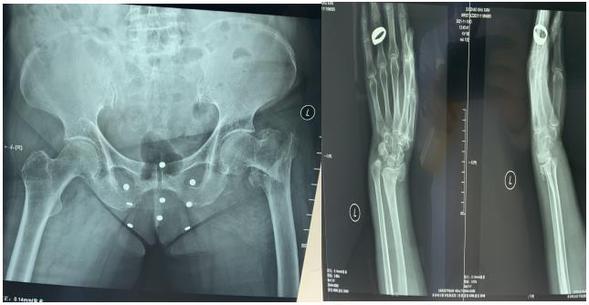

术前X线

冬季到了,雪大路滑,走路时摔伤几率增加。特别是老年人骨质疏松多见,常常因摔伤后导致骨折病例不在少数。近日,骨三科收治一位老年患者,77岁,在小区门口走路时不慎摔倒,伤后即感左腕部及左髋部疼痛、肿胀伴活动受限,在家属陪同下由120救护车送往我院急诊,急诊医师查体后行左腕部及左髋部X线明确为左股骨粗隆间骨折、左桡骨远端骨折、左尺骨茎突骨折,为求进一步诊疗入住我院骨外三科。